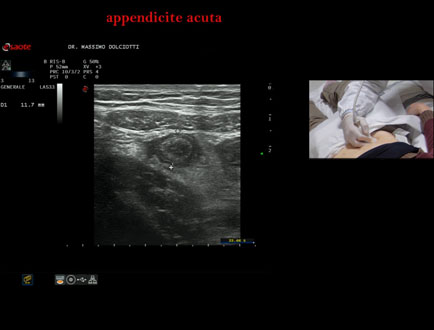

Età Paziente: M 22 anni

Motivazione dell'esame: da un giorno dolori addominali in sede ileo-cecale.

Commento all'esame: le immagini ed il video documentano, in sede ileo-cecale, appendice di spessore aumentato (9 - 10 mm - V.N. inferiore a 6 mm) con incremento della vascolarizzazione. Gli elementi ecografici segnalati orientano per appendicite acuta.

Conclusioni: appendicite acuta (acute appendicitis).

In collaborazione: Dr.ssa Marica Manfredi - Ancona, Dr. Ilir Qose - Ancona

Presentazione: Dr. Massimo Dolciotti - Ancona